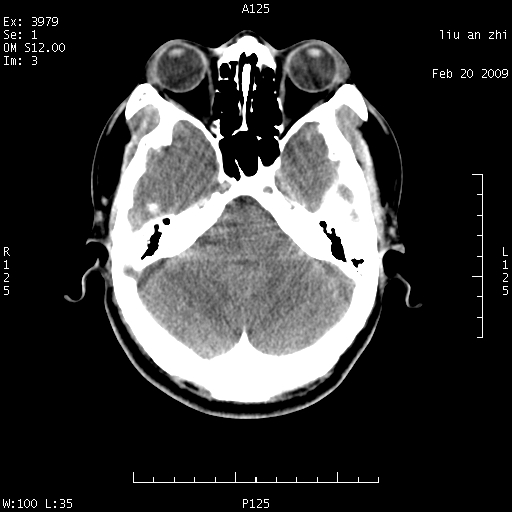

患者:男,32岁 被打伤后3天,自感头昏头痛作头颅ct检查。请大家看一下想什么??

请注意小脑幕!!!

考虑左侧天幕硬膜下血肿。

密度不够,不能诊断sah.正常小脑幕密度可稍高。

考虑小脑幕积血。

ct18448的结果:mri检查左侧天幕下血肿